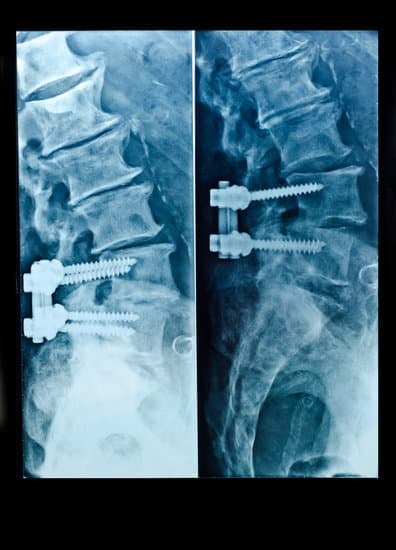

고정 장치의 설치: 척추를 원하는 위치에 고정시키기 위해 금속 막대, 나사, 케이지, 판 등의 장치를 사용합니다.

이러한 고정 장치는 척추가 올바른 정렬을 유지하도록 도와주며, 유합이 진행되는 동안 뼈가 움직이지 않도록 지지합니다.

뼈 이식: 척추 뼈 사이에 뼈 이식재를 삽입하여 두 뼈가 자연스럽게 유합될 수 있도록 합니다.

고정 장치 설치: 금속 막대, 나사, 판 등을 사용하여 척추를 고정시키고, 유합 과정을 지원합니다.